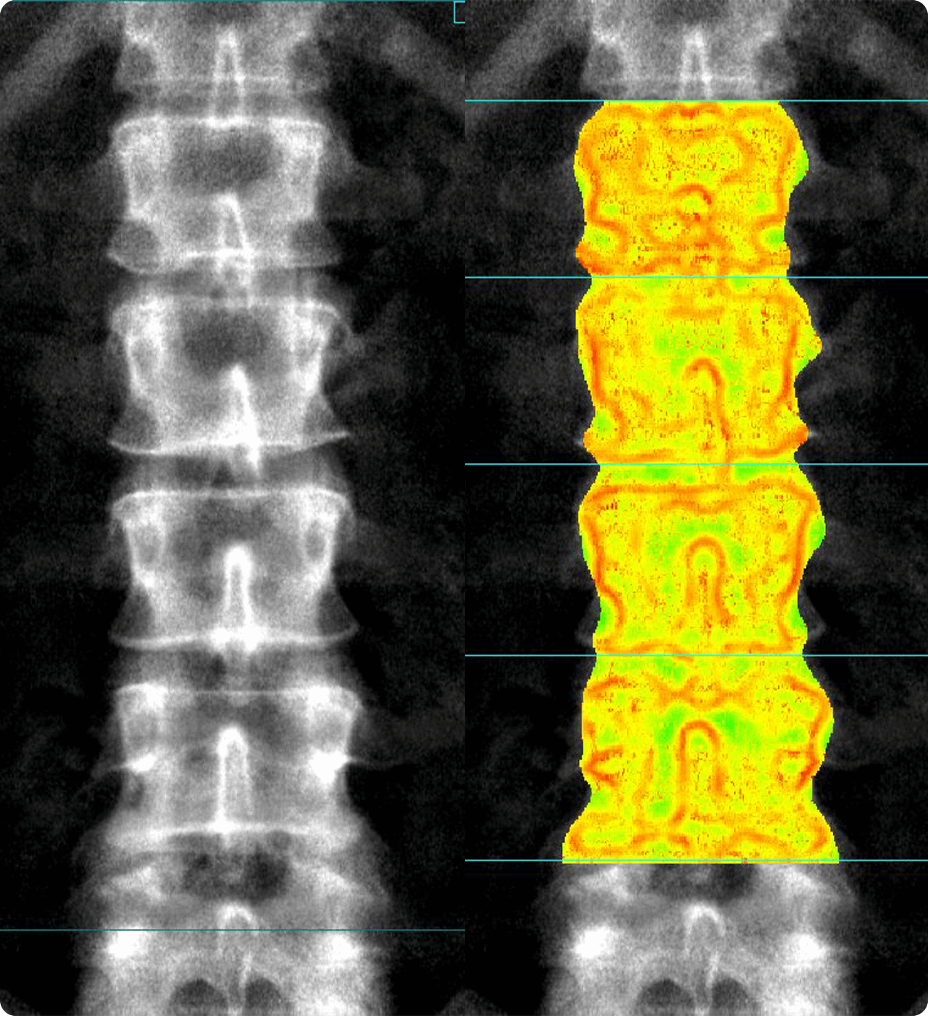

Score osseux trabéculaire (TBS) intégré2 L’application Score osseux trabéculaire (TBS) utilise une acquisition DXA du rachis AP pour évaluer la micro-architecture des os et fournir un score TBS. Cette application en option permet d’avoir une meilleure compréhension de la qualité des os (en plus de la quantité d’os grâce à l’analyse de la DMO), afin d’offrir des informations supplémentaires sur la santé osseuse du patient. Combiné à la DMO et au FRAX, le TBS peut être particulièrement utile pour évaluer les patients dont la DMO est à la limite de l’ostéoporose. Image à droite : Compte rendu sur la santé osseuse